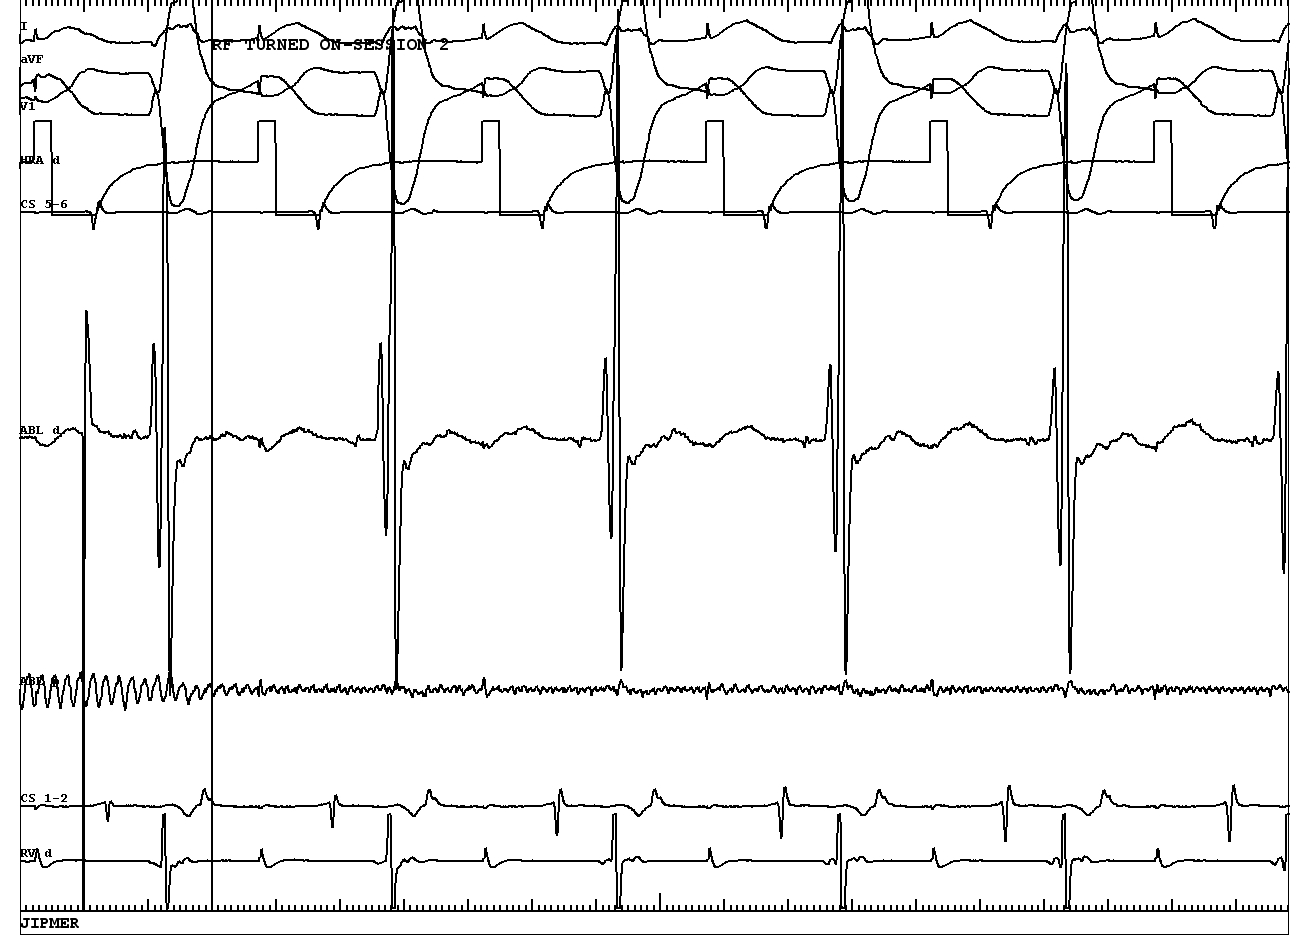

Ablation

09a_succ_ablation.JPG